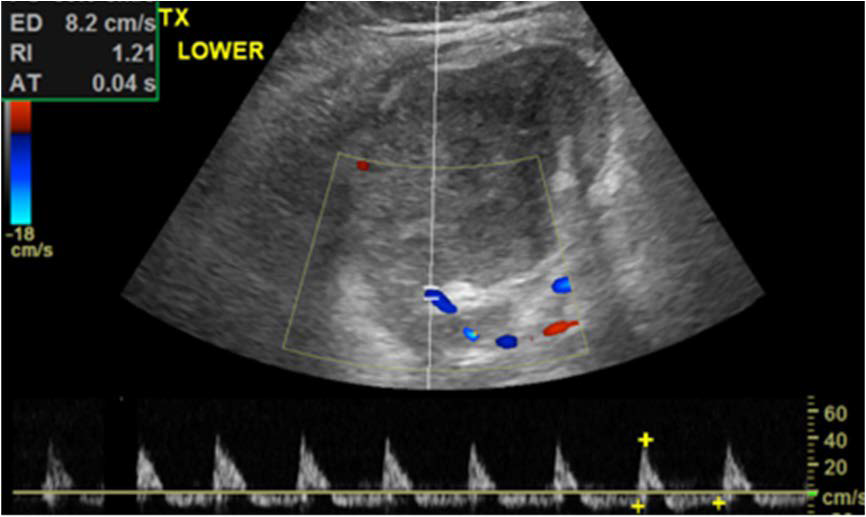

Figure 2: Doppler ultrasound image of the renal allograft showing reversal of diastolic blood flow in lower pole of transplanted kidney.